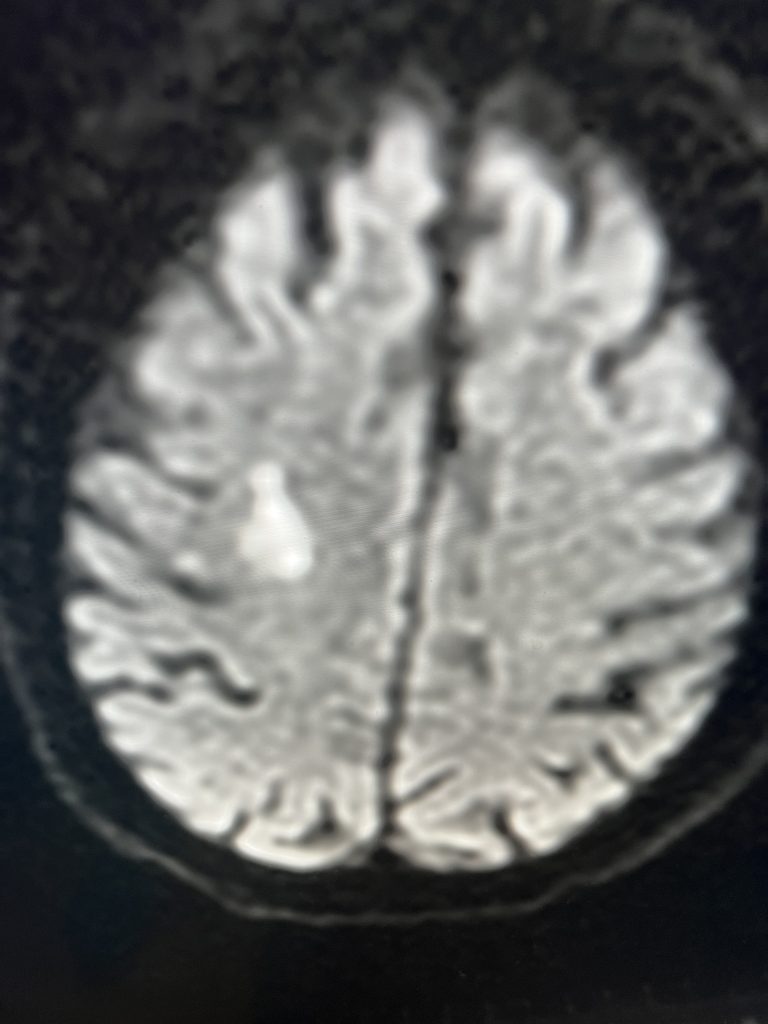

Fig. 1 – Pre-operative imaging using a diffusion-weighted image sequence, shows multiple areas of most likely embolic stroke in the right frontal white matter.

MRI imaging using the diffusion-weighted image sequence, which is highly sensitive for acute stroke showed multiple areas of most likely embolic stroke in the right frontal white matter (Figure 1) as well as the right corona radiata (Figure 2).